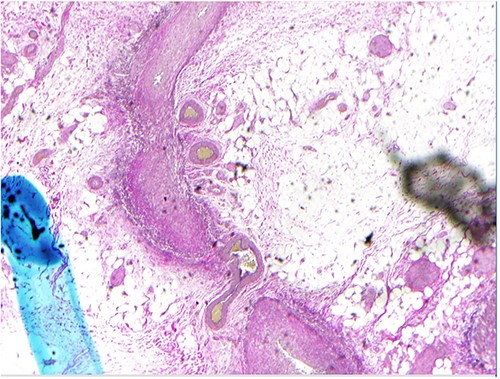

Due to the patient’s increasing abdominal pain, with focal left-sided peritonitis, tachycardia and elevated white count, she was taken to the operating room for abdominal exploration. Intraoperatively, she was noted to have ‘woody’ inflamed sigmoid and descending colon. Segmental resection of the proximal descending colon to the upper rectum with an end colostomy was performed. The surgical pathology showed focal, acute inflammation, ulceration and fibropurulent exudates as well as active and healed necrotizing arteritis with ischemic ulcer (Fig. 3). Small- and medium-sized vessel walls were noted to be thickened with necrosis in some areas and disruption of the internal elastic lamina. A few arteries showed mixed inflammatory infiltrates in the media. Overall, this pathology of necrotizing arteritis was consistent with features of PAN.

As evidenced by this case, there is no laboratory testing specific for PAN [5]. Diagnosis of concurrent hepatitis can influence management, and imaging can be helpful in the work-up of potential vascular abnormalities. Our patient’s abdominal CTA showed multiple aneurysms, leading us to work up vasculitis as an etiology for her colitis. In an otherwise healthy patient who presents with multiple aneurysms on imaging, PAN should be on the differential diagnosis. Biopsy results are the gold-standard for definitive diagnosis, and in this clinical scenario, her colon biopsy showed active and healed necrotizing arteritis with an ischemic ulcer and contained features consistent with PAN.